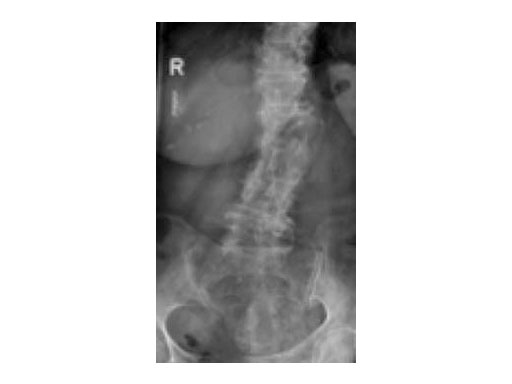

A 78-year-old woman was affected by steroid induced osteoporosis. She had persisting pain (mechanic and muscular) due to static imbalance (hyperkyphosis) and nonunion 8 months after a minor trauma with a vertebral compression fracture and vertebra plana of L1, and development of symptomatic stenosis of the spinal canal with loss of mobility over time. Pre-existing degenerative lumbar scoliosis was increased by the fracture.